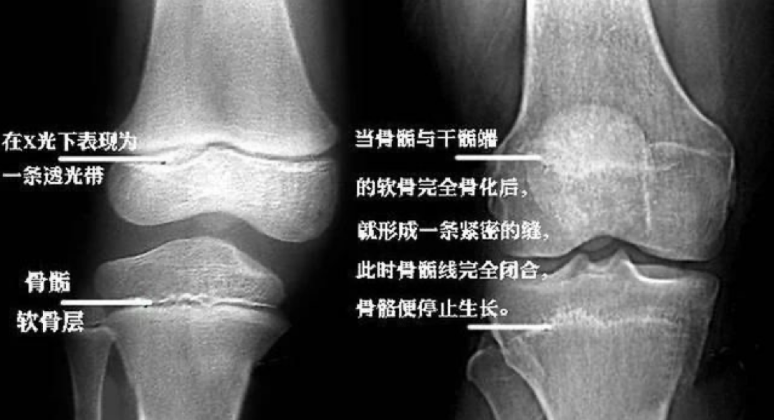

骨骺是骨在发育过程中,骨两端的软骨中出现的骨化点。而骨骺线,就是骨骺与干骺端之间的软骨,在儿童的X光片上表现为一条较宽的透光带。

骨骺线与一般的终身不骨化的软骨(如耳软骨,鼻软骨等)不同,会随着生长逐渐骨化。也就是说,只要它存在,就会不断骨化,从而延长存在于四肢的长骨,助力身高增长。

当孩子的年龄增长时,骨骺线也会随之缩短,最终变成一条缝,自此骨骺线完全闭合,骨骼停止生长。